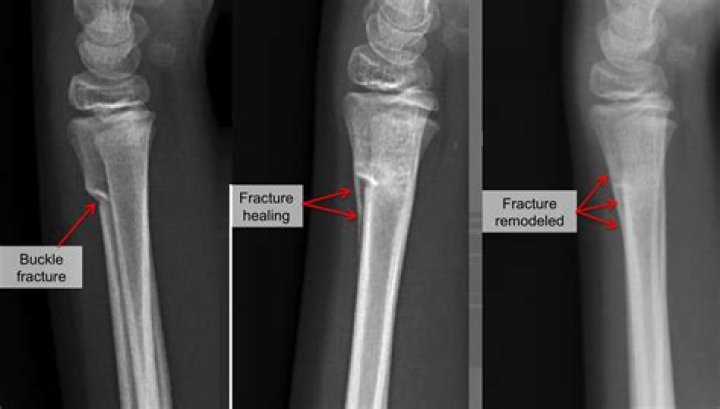

A buckle (or torus) fracture is a type of broken bone. One side of a bone bends, raising a little buckle, without breaking the other side of the bone.

A buckle fracture is best treated with a splint rather than a full circular plaster cast. Because the bones are only partially broken, they heal very well within a few weeks with the support and protection that a splint provides.

Buckle fractures are non-displaced stable fractures, meaning that the bone did not move. They can be treated with either a wrist splint or a short arm cast, both of which give the fracture the protection it needs to heal.

A buckle fracture in the wrist is a small area of compressed bone. Your child should wear a removable backslab (partial cast) or splint for three weeks. A sling may help reduce discomfort. Most children will not need a follow-up appointment or X-ray, because buckle fractures usually heal quickly without any problems.